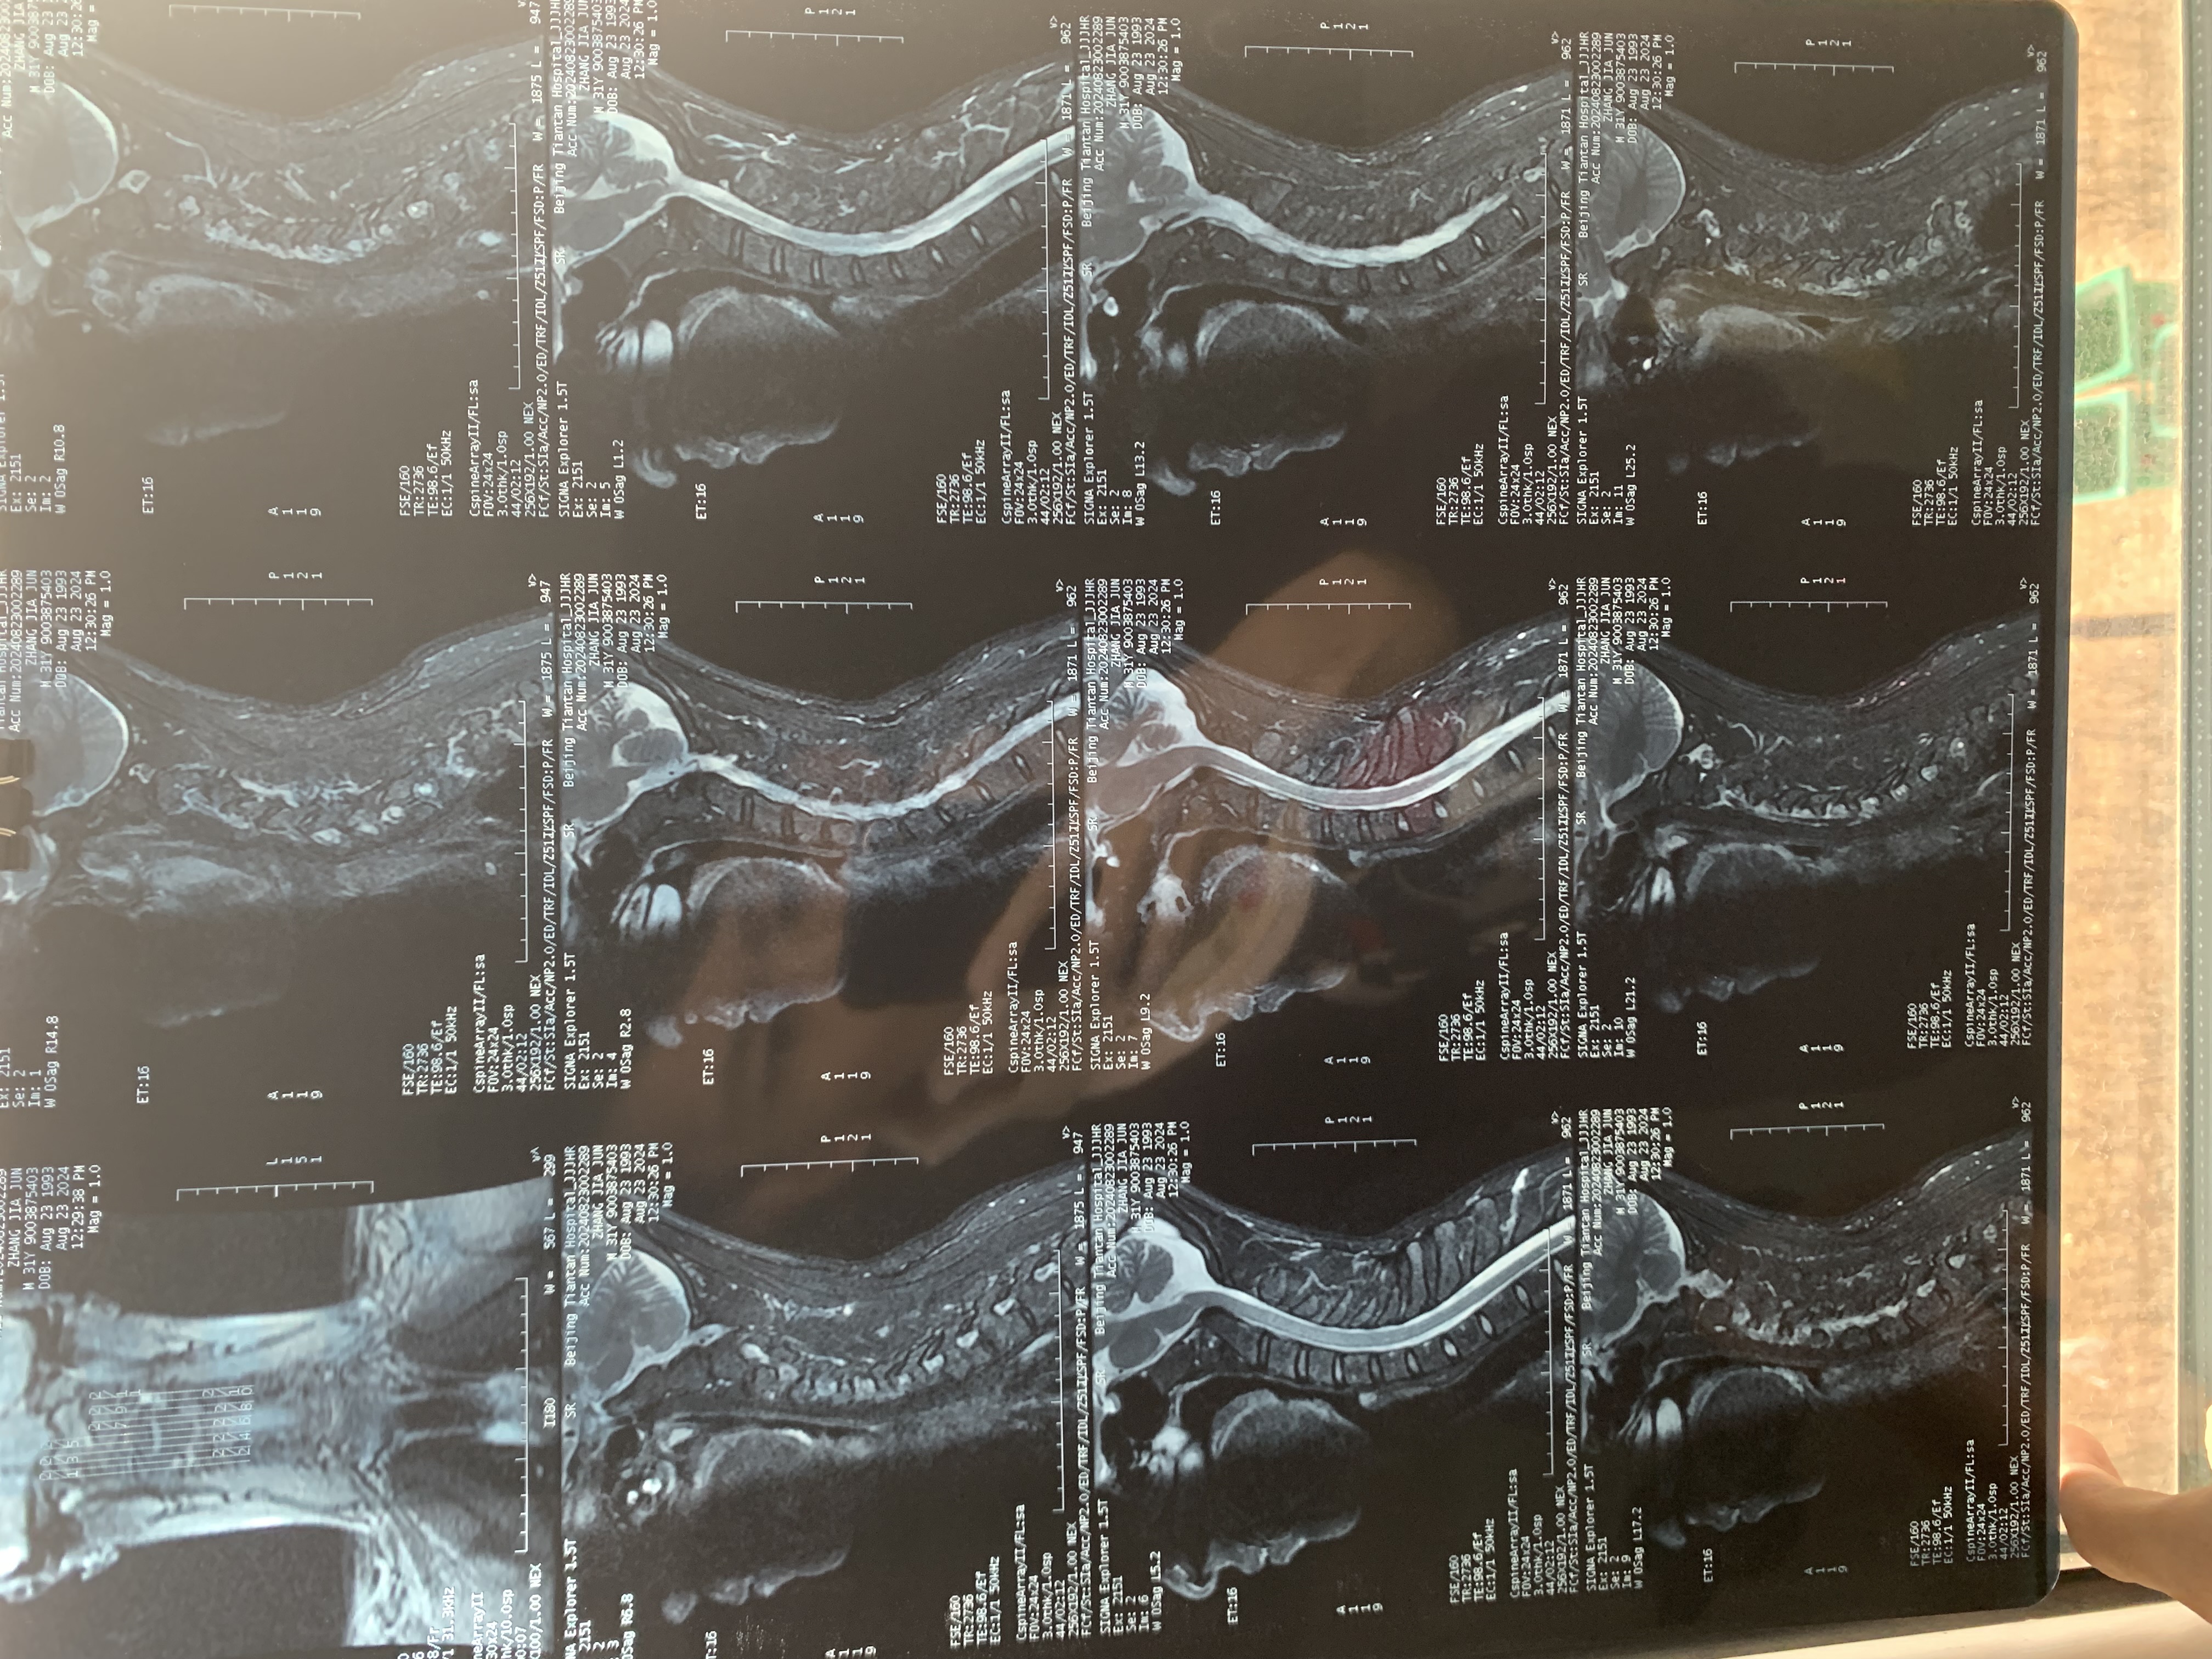

• 2024.12.13,去北京拍片,当天走路有点多,感觉脑袋里面疼。影像报告脱位和颅底凹陷都还在,影像如下: